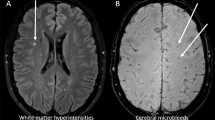

SVD affects the microvasculature of the brain and is visible on magnetic resonance images (MRI) by its manifestations, which include white matter hyperintensities, cerebral microbleeds, lacunar infarctions, and cortical superficial siderosis [6]. Although common in type 1 diabetes, SVD remains scarcely studied [5]. Within the Finnish Diabetic Nephropathy (FinnDiane) Study, we have found increased blood pressure [5, 7], carotid intima-media thickness [8] and the severity of diabetic retinopathy [9] to be associated with SVD in individuals with type 1 diabetes. Other studies have likewise linked SVD with arterial stiffness [10] and diabetic retinopathy [11]. In addition, SVD has been suggested to associate with the haptoglobin (Hp) genotype [12].

Brain-MRI was performed at the Helsinki Medical Imaging Center, Helsinki University Hospital, with a 3.0 Tesla scanner (Achieva, Philips, Best, The Netherlands). Images were assessed for markers of SVD by an experienced neuroradiologist (J.M.). As markers, we considered white matter hyperintensities (a score of ≥ 1 on the Fazekas scale), cerebral microbleeds, lacunar infarctions, and superficial siderosis, based on standardised criteria [27]. The neuroradiologist was blinded to all clinical data. Brain-MRI and assessment of the images have been described previously in further detail [5]. For analysis, a participant with a positive finding of any marker was considered to display SVD. The different markers were also analysed categorically as separate manifestations of SVD, i.e., presence versus absence of the specific manifestation.

The study participants had a mean age of 38.8 ± 7.3 years, 95 (53.1%) were women, participants had a mean diabetes duration of 23.3 ± 10.1 years, and their mean HbA1c was 8.1 ± 3.5% (65 ± 12 mmol/mol). None of the participants had peripheral arterial disease. A total of 62 (34.6%) participants had SVD. Cerebral microbleeds were observed in 40 (22.3%), white matter hyperintensities of Fazekas ≥ 1 in 31 (17.3%), and lacunar infarctions in four (2.2%). None of the participants had cortical superficial siderosis. White matter hyperintensities and cerebral microbleeds were observed simultaneously in nine participants. All four participants with lacunar infarctions had some additional manifestation: two had white matter hyperintensities and the other two had cerebral microbleeds.